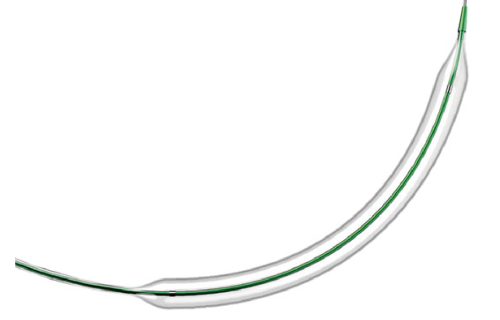

Na área de Cardiologia Intervencionista, fornecemos dispositivos de ponta, como stents, cateteres e balões, que são essenciais para a realização de angioplastias e outros procedimentos cardíacos minimamente invasivos. Nossos produtos são projetados para oferecer máxima eficiência e segurança, contribuindo para a rápida recuperação dos pacientes e a redução de complicações pós-operatórias.

Em Cirurgia Vascular, Endovascular e Radiologia Intervencionista oferecemos uma ampla gama de soluções, incluindo enxertos endovasculares, cateteres de trombectomia e dispositivos de embolização. Esses produtos são vitais para o tratamento de doenças vasculares complexas, como aneurismas e tromboses, proporcionando aos profissionais de saúde as ferramentas necessárias para intervenções precisas e eficazes.

Nossa atuação em Neurorradiologia Intervencionista inclui a oferta de microcateteres e stents especializados para o tratamento de aneurismas cerebrais e outras condições neurológicas críticas. Esses dispositivos são desenvolvidos com tecnologia de ponta para garantir a máxima segurança e eficácia durante os procedimentos, ajudando a preservar a integridade cerebral dos pacientes.